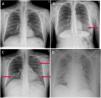

ResultadosEl 91,4% de los pacientes precisaron ingreso. Existe una asociación estadísticamente significativa entre la escala ERVI y la necesidad de ingreso hospitalario (p=0,03). El ingreso en UCI presenta una asociación significativa con la escala ERVI (p<0,001). Han fallecido 51 (17,5%) pacientes, de los cuales el 57% presentaba una escala ERVI grave. Cuando estudiamos la mortalidad agrupando a los pacientes según su resultado en la escala ERVI y su rango de edad, el porcentaje de fallecidos aumenta a partir de los 70 años en los pacientes con una escala ERVI moderada y grave.

ResultsHospital admission was necessary in 91.4% of the patients. The RSEHA was significantly associated with the need for hospital admission (p=0.03) and with the need for ICU admission (p<0.001). A total of 51 (17.5%) patients died; of these, 57% had the severe pattern on the RSEHA. When we analyzed mortality by grouping patients according to their results on the RSEHA and their age range, the percentage of patients who died increased after age 70 years in patients classified as moderate or severe on the RSEHA.